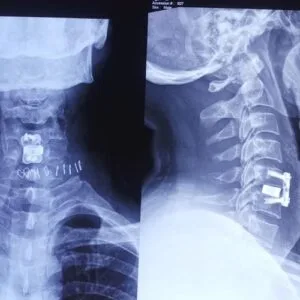

The Best Spine Specialist at Surat Spine Hospital uses updated and safe treatment methods. These include minimally invasive procedures, targeted physiotherapy, accurate imaging and modern pain-relief techniques. Each treatment is selected based on your condition, age and lifestyle. The Spine Specialist also works closely with trained therapists to support long-term spinal health.

Spine issues come in many forms. The Best Spine Specialist treats slipped discs, sciatica, spinal stenosis, nerve compression, spondylosis, posture-related pain and age-related degeneration. Sports injuries and accident-related spine problems are handled with care. Instead of treating only the pain, the Spine Specialist focuses on the root cause so the problem does not return.